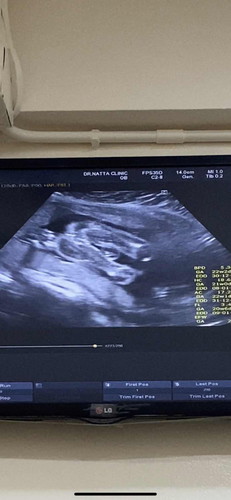

เพศหญิงหรือชายน้าา….?

แม่ๆคิดว่ายังไงกันบ้างคะ น้องเป็นเพศหญิงหรือชาย คุณหมอแอบบอกมาแล้วค่ะแต่แม่ยังไม่ค่อยมั่นใจ😅##ขอบคุณสำหรับคำตอบค่ะ

ผญ จ้าแม่ บ้านนี้ก็มี2กลีบแบบนี้เลย

เหมือนน้องมีไข่ ผช.มั้ยค่า😅😅

คุณหมอบอกว่าน่าจะผู้หญิงค่ะ แม่อยากได้ลูกสาวแต่ก็แอบกลัวว่าน้อนจะเป็นไข่🤣